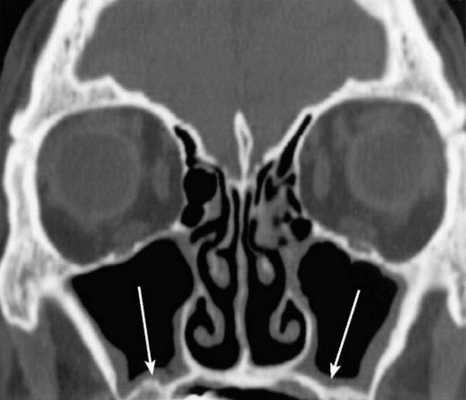

КТ носовых пазух (фронтальный срез). Стрелками отмечено утолщение слизистых оболочек